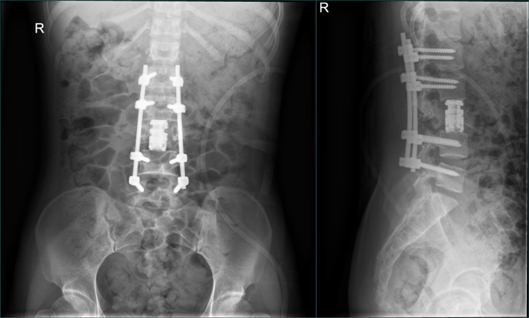

小郑的手术十分顺利,在回到病房之后,她的双脚终于能动了。经过一段时间的康复锻炼之后,小郑从双下肢的不完全瘫痪,到可以主动进行抬腿、抬脚,甚至能够完成踢腿动作,双下肢的肌力也从0级恢复到4级。

复查的影像检查结果也显示,小郑腰椎的植入物位置良好,脊髓和神经的压迫都消失了。此后,小郑还需要进行一系列的康复治疗,以获得更好的恢复。

术后1周余复查腰椎X片、CT和MRI)